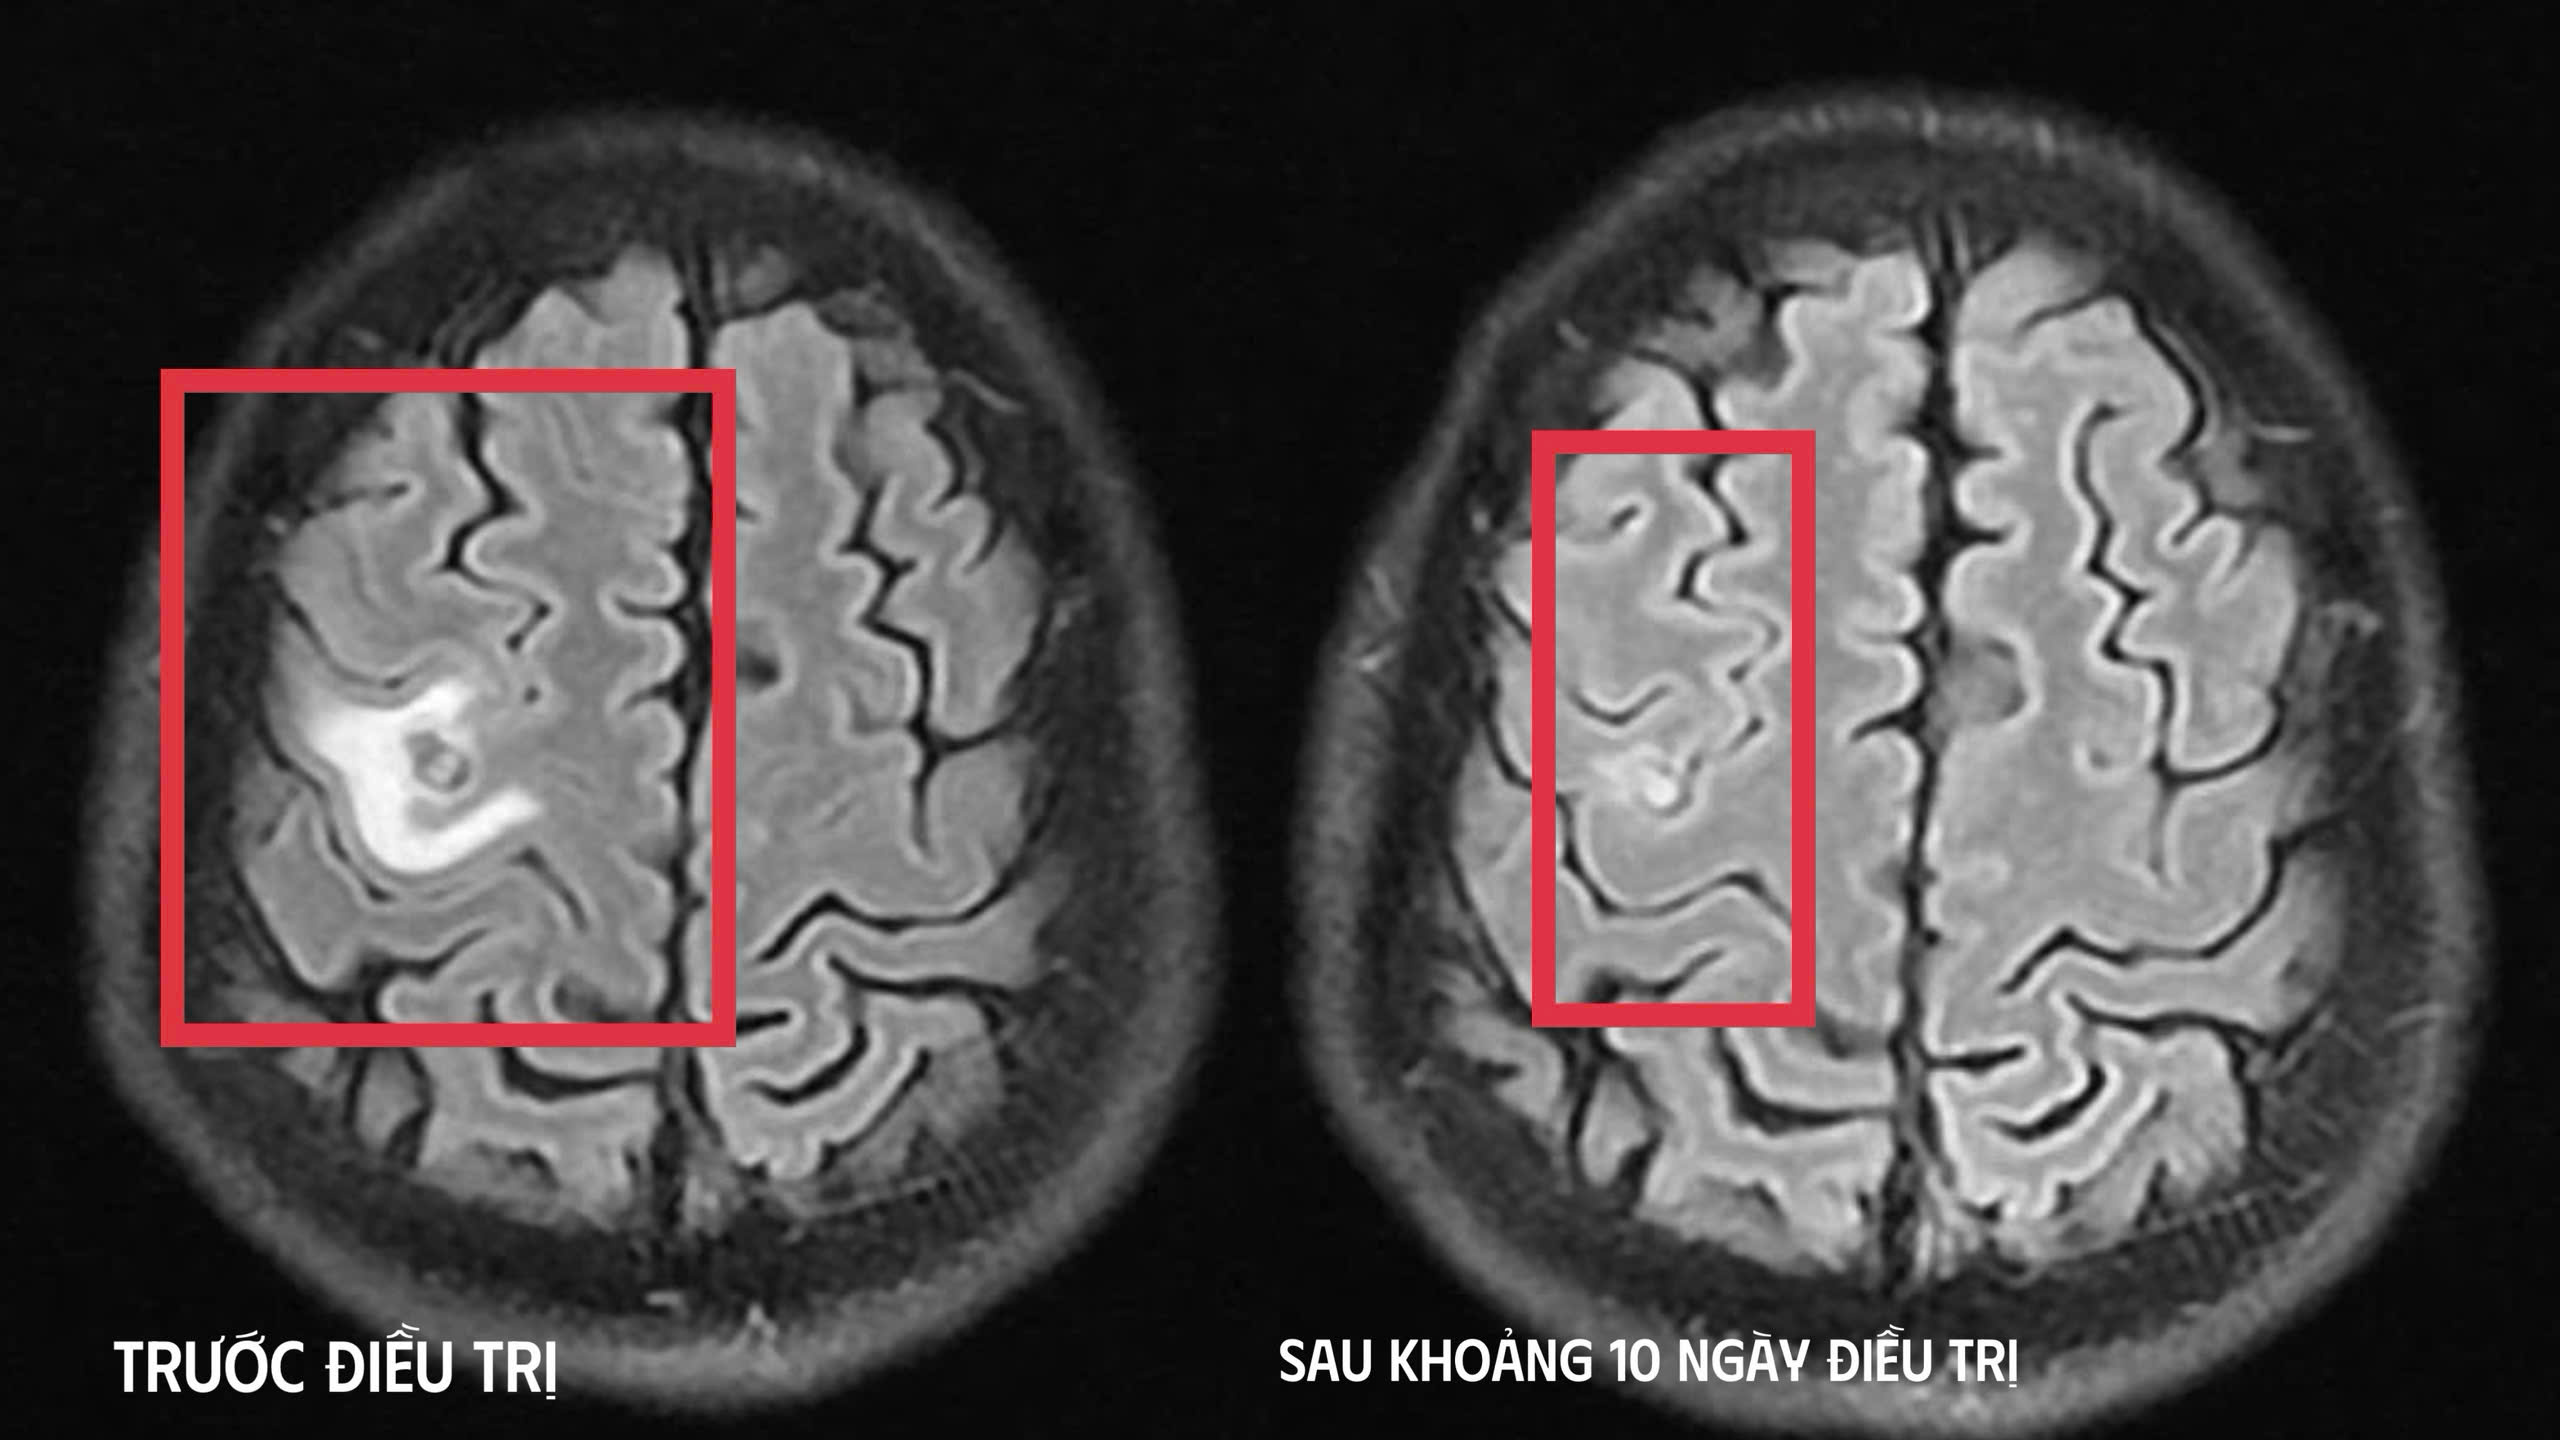

Kết quả chụp cộng hưởng từ (MRI) sọ não cho thấy một tổn thương dạng nang nhỏ tại thùy trán trái, kích thước khoảng 11 x 7 mm, xung quanh có phù não nhẹ. Hình ảnh này gợi ý nhiều đến tổn thương do ký sinh trùng hơn là u não nguyên phát.

Hình ảnh chụp chiếu trước và sau khi điều trị (Ảnh: BVCC).

Sau khoảng 10 ngày điều trị nội trú, tình trạng bệnh cải thiện rõ rệt như hết tê tay, không còn cơn co giật, không đau đầu hay chóng mặt, toàn trạng ổn định. Người bệnh được cho ra viện và tiếp tục điều trị ngoại trú đủ liệu trình kéo dài 4 tuần.

Khi tái khám gần một tháng sau, phim MRI cho thấy tổn thương não thu nhỏ rõ rệt, phù não giảm, không còn dấu hiệu tiến triển, chứng tỏ đáp ứng điều trị tốt. Bệnh nhân được chỉ định thêm một đợt thuốc củng cố và theo dõi lâu dài.